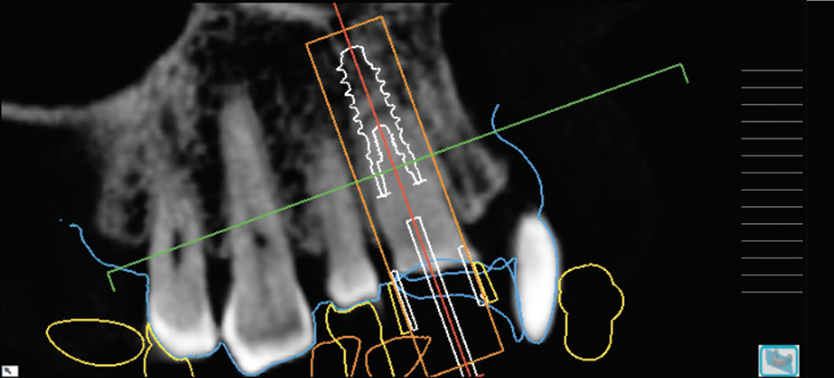

(5.) Radiographic assessment of the mandibular right first molar ridge form, including 3D evaluation of the septal/buccal, lingual, and apical bone for implant stabilization. The goal is to restoratively center the implant.

Figire 5